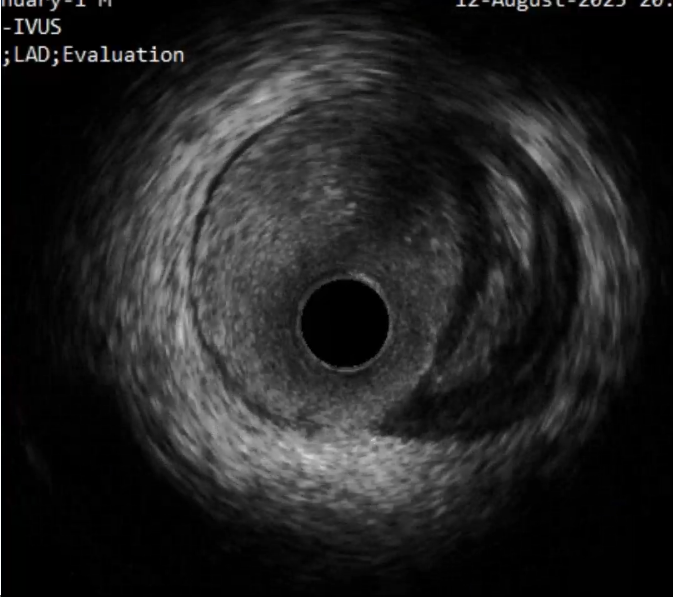

首先进行正向准备,对角支回撤IVUS明确CTO入口,Pilot200导丝进入

IVUS证实导丝进入CTO入口正确